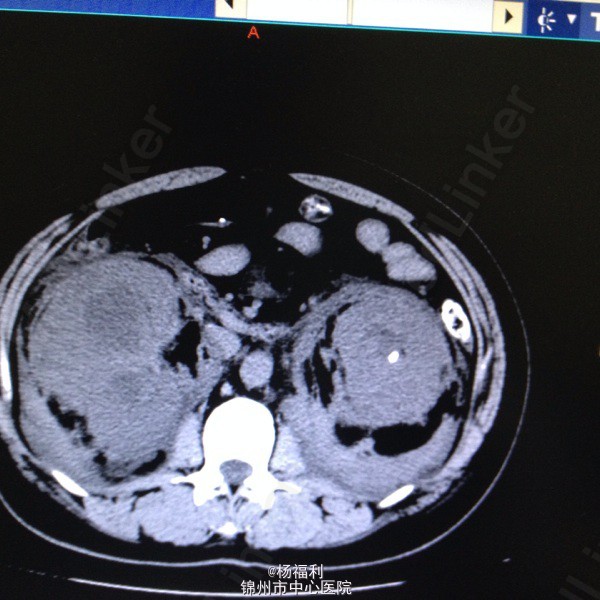

44岁女患。为消化科我会诊患者。 现病史:以上腹痛9小时为主诉入院。无发热及寒战、噁心未呕吐,无腹泻及黑便。 既往史:双眶炎性假瘤2年,口服激素治疗,并补钾。

查体:上腹部压痛,无反跳痛、右侧压痛明显,右肾区叩击痛,左肾区轻叩击痛,双输尿管走形区无压痛。 辅助检查;泌尿系彩超:双肾积水。 血白细胞:9.99*10^9。 肾功能正常。 全腹部ct及MRU检查:见图片。

诊断;真的不知道是啥病。 处理:暂时止痛处理。双肾病变。不知从哪里下手。